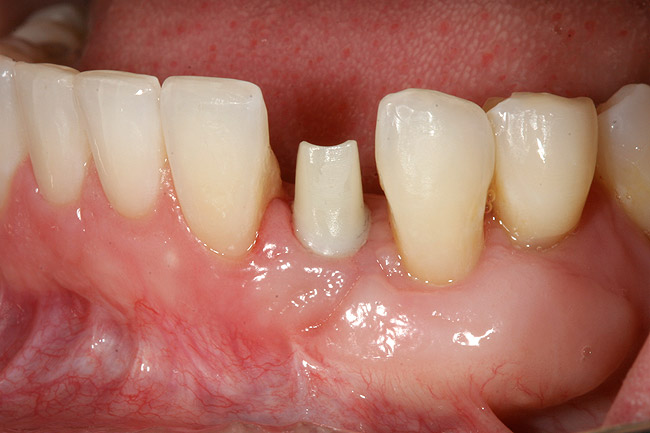

The patient had no medical concerns and had a history of an implant placement in December 2002 when she was 25 years old. In February 2005, she presented with a mobile implant and an associated advanced peri-implantitis. Radiographic review at the initial examination demonstrated significant destruction of the dentoalveolar ridge around the implant as well as around the adjacent natural dentition. Emergency-based treatment involved surgical implant removal only and debridement of the infection (Figure 4 and Figure 5). Following uneventful healing, an advanced ridge defect was apparent at the edentulous site and moderate and advanced attachment loss noted at No. 22D and No. 21M, respectively (Figure 6 and Figure 7). This case demonstrates bone loss of two separate origins: lack of bone because of tooth agenesis and destruction of bone from inflammatory peri-implantitis.

Figure 6  Mucogingival and residual defect after removal of implant in site No. 22.

Figure 6